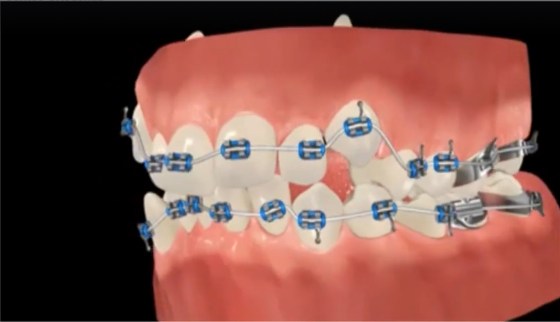

Os cuidados com a higiene bucal são importantes porque a boca é o órgão receptor dos alimentos. Dentes fortes e boca saudável: é sinônimo de boa alimentação, higiene constante e bem feita. Dessa forma, é possível concluir que quando alguém se alimenta bem e tem hábitos de higiene bucal corretos, ela evita doenças como a gengivite, as cáries e o incômodo mau hálito.

Além da questão estética, os cuidados com os dentes garantem uma dicção correta (a forma de pronunciar as palavras) e uma mastigação mais benéfica. Os cuidados devem ser diários, a escovação deve ser feita pelo menos três vezes ao dia e o fio dental tem que ser usado em seguida.

Esses hábitos são preventivos; através deles é que evitamos as doenças bucais que causam a perda dos dentes. Eles devem ser adquiridos na infância e as crianças devem entender a importância de fazer todos esses procedimentos e os pais precisam levá-las frequentemente ao dentista.